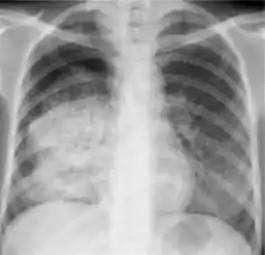

Chest x-ray showing coarse reticulonodular densities on the lower right lung of post-primary pulmonary TB.

Chest x-ray of Ghon's complex of active tuberculosis